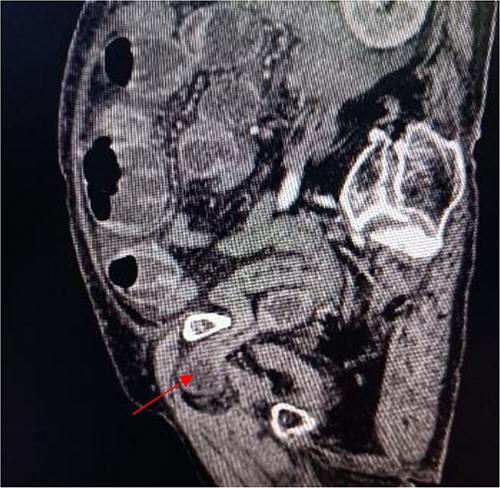

Coronal view shows right obturator hernia entering the intestinal canal (indicated by red arrow).